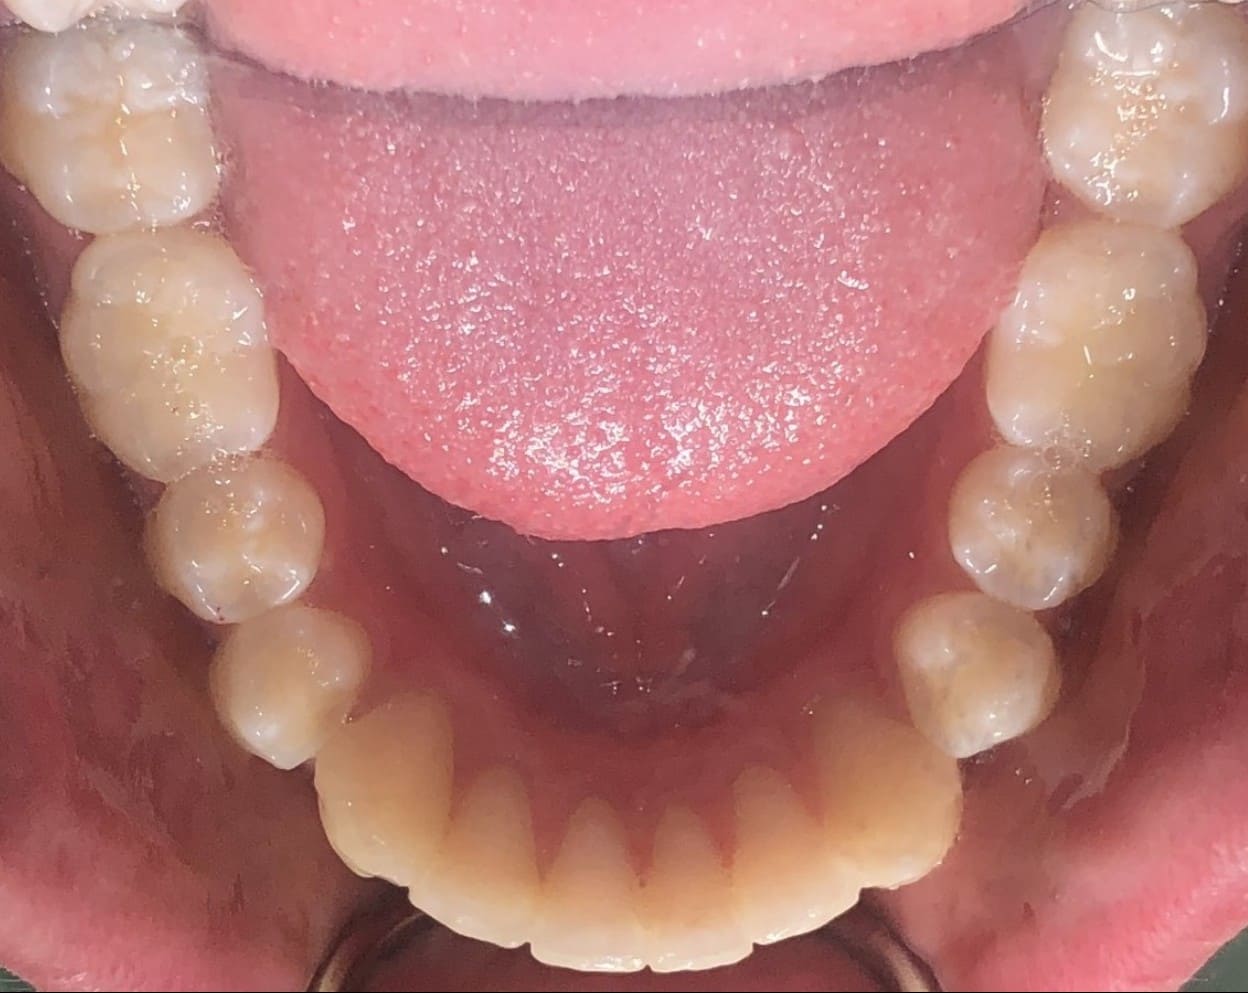

Initial